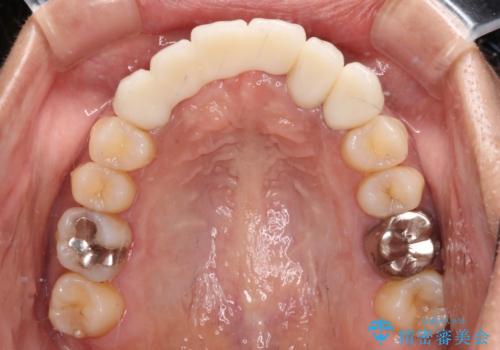

1回の歯肉移植により歯肉の厚みは大幅に改善されましたが、折角なのでもう少し大きくしたいとの要望があり、2回目の処置も行うこととしました。

厚みも高さも十分な歯肉量を獲得することができました。